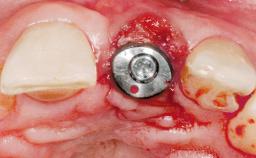

Immediate Placement of an Implant in a Maxillary Left Central Incisor Site

A 33-year-old female patient presented with an upper left central incisor that required extraction after a failed endodontic therapy. The tooth had been traumatized when the patient was a teenager and had undergone several endodontic treatments, including two apicectomy procedures. The patient was in good health and did not smoke. Clinical examination showed that the patient had a high lip line. In full smile, the gingival margins of the upper teeth were visible to the first molars. The gingival margins of central incisors 11 and 21 were only just showing. Examination of tooth 21 confirmed that the tooth was mobile and had hypererupted by 1 mm.

| Placement Protocol | Immediate implant placement |

| Tooth Site | Maxillary incisor or canine |

| Socket Morphology | Single-root socket |